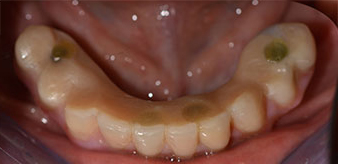

The 64-year-old patient presented with residual dentition of teeth 38, 33 and 43 and a clasp denture in the mandible (Fig. 1 and 2).